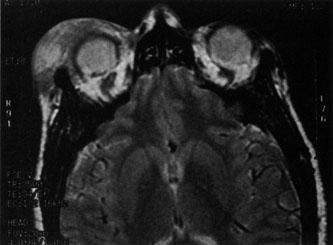

A subperiosteal abscess may rupture or invade the periorbit, resulting in an orbital abscess. This may or may not be contiguous with the subperiosteal collection on CT. There may be gas or air–fluid levels within the mass.51,56,58,59 An orbital abscess may present as an enhancing ringlike peripheral mass that can be either heterogeneous or homogeneous (Fig. 18).

Fig. 18. Orbital abscess. A. Computed tomography of an orbital abscess presenting as an enhancing intraconal mass on right side. B. T1-weighted image. C. T2-weighted image. Note area of high signal corresponding to abscess.